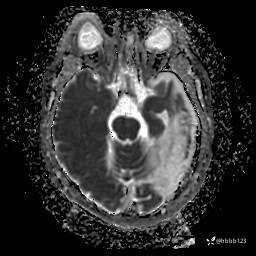

ADC: